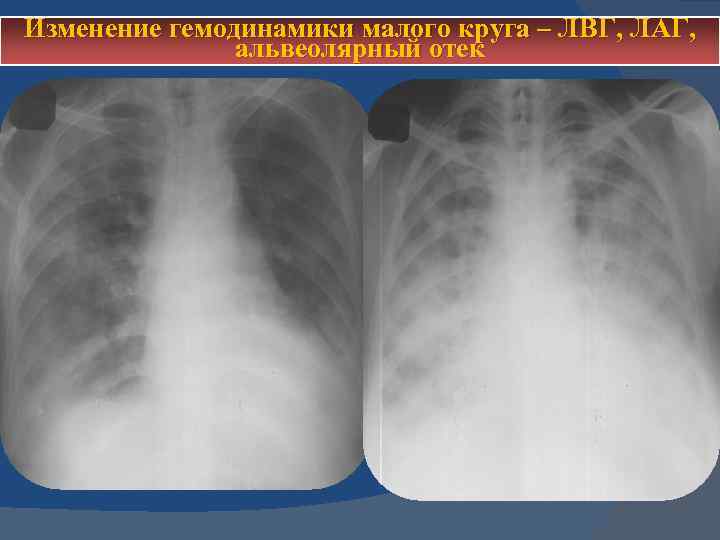

Изменение гемодинамики малого круга – ЛВГ, ЛАГ, альвеолярный отек